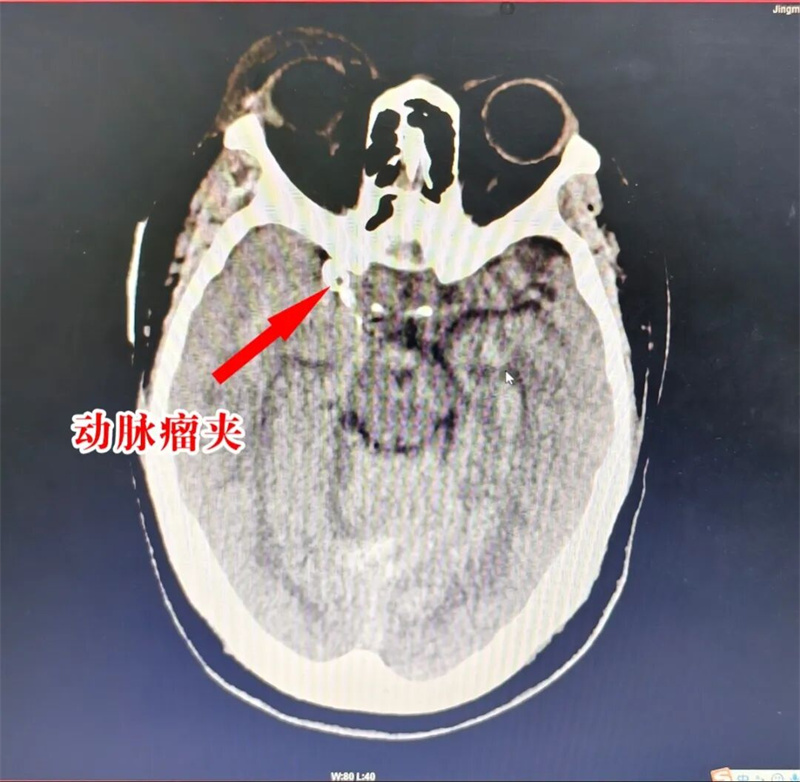

术后CTA显示:破裂的动脉瘤成功夹闭

术后CT提示:颅内出血较术前减少、吸收

迅速阻断右侧颈内动脉后,随着“咔嗒”两声,两枚动脉瘤夹果断夹闭瘤颈及部分瘤体,随即造影显示动脉瘤夹闭完全,载瘤动脉及重要穿支血管血流通畅,没有出现缺血迹象。